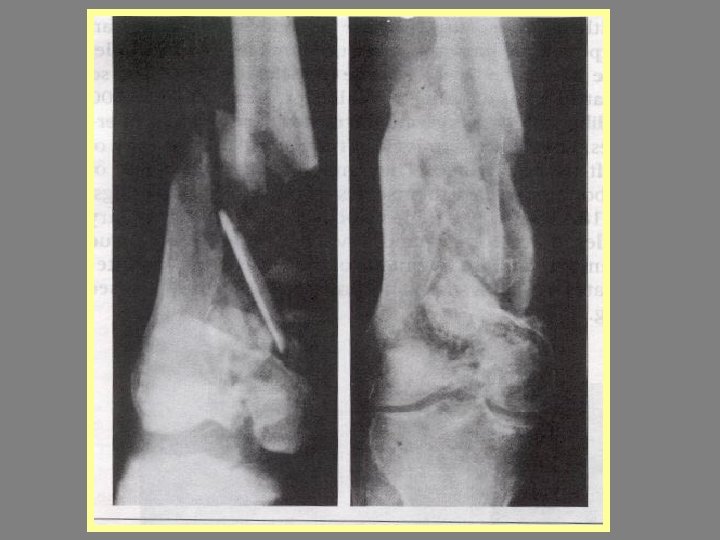

Open fracture treatmennt Emergency Definitive

EMERGENCY 1 -CULTURE 2 -IRRIGATION 3 -ANTIBUTIC 4 -DRESSING 5 -ANTITETANIC 6 -SPLINTING 7

EMERGENCY 1 -CULTURE 2 -IRRIGATION 3 -ANTIBUTIC 4 -DRESSING 5 -ANTITETANIC 6 -SPLINTING 7 -NEUROVASCULAR

Difinitive 1 -DEBRIDMENT 2 -FRACTURE TREATMENT A-INTERNAL FIXATION B-EXTERNAL FIXATION 3 - SKIN